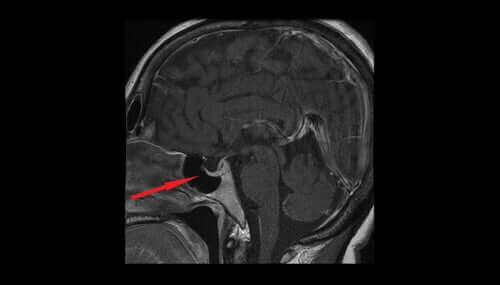

Vasopressin, også kendt som antidiuretisk hormon eller ADH, kommer ud af hypothalamus´ magnocellulære kerne. Derfra passerer det videre til neurohypofysen og til sidst ind i blodbanen.